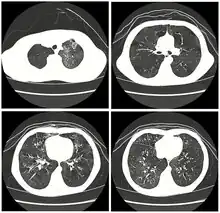

High resolution CT scan of a child with post-infectious obliterative bronchiolitis showing glass pattern with air trapping and bronchial thickening

Typically found in young children and is the most common cause at this age.[31] Generally occurs after a viral infection of adenovirus (types 3, 7, and 21), measles (rubeola), mycoplasma, CMV, influenza, and parainfluenza.[4][6] Swyer-James syndrome is a rare complication of obliterative bronchiolitis caused by measles or adenovirus.[32] Post-infectious obliterative bronchiolitis is most common in the southern hemisphere particularly in countries such as Brazil, Argentina, Australia, Chile and New Zealand.[33] There was a large prevalence of the disease in these areas during the 1990s and early 2000s. In one hospital in Buenos Aires, the Ricardo Gutiérrez Children's hospital, the disease accounted for 14% of their inpatient respiratory population from 1993 to 2002.[33] As such, much of the information about post-infectious obliterative bronchiolitis has come from research out of South America. The most significant risk factors for the disease are infection with adenovirus and the need for ventilator support.[33] In contrast with another cause of obliterative bronchiolitis in children, Steven's Johnson's syndrome, post-infectious obliterative bronchiolitis tends to be a chronic but non-progressive disease.[31] The disease can have varying impact on children and their quality of life, which has been studied by lung function tests, as well as their exercise tolerance.[34] Children with lower lung function based on their pulmonary function testing, have lower exercise tolerance, which compounds the impact of the disease on cardiovascular function as they are not able to maintain age appropriate aerobic fitness.[34] This ultimately affects their activities of daily living (ADLs) and their quality of life going forward.[34]